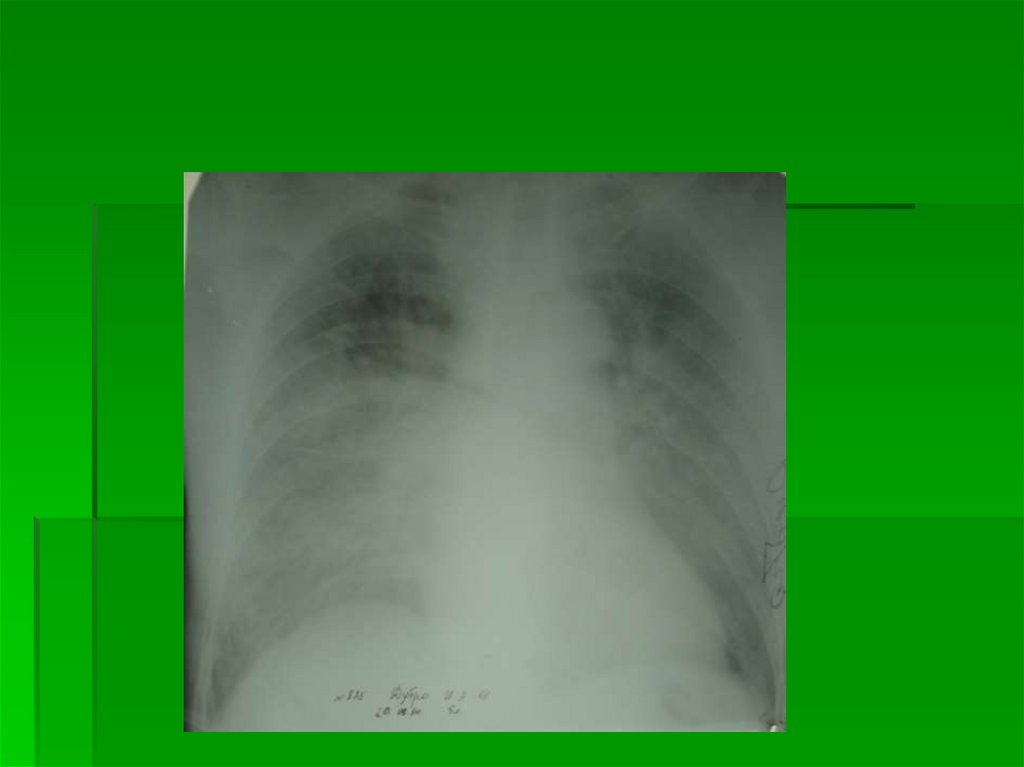

4 степень

Альвеолярный отек легких

Инфильтративно-подобный отек легких

Ограниченное затемнение в пределах

нижнего или среднего и нижнего легочного

поля, может быть односторонний

Дифференциальной диагноз – с пневмонией:

Оценить состояние МКК (Rn-признаки ЛВГ)

Обратная динамика за сутки

36.